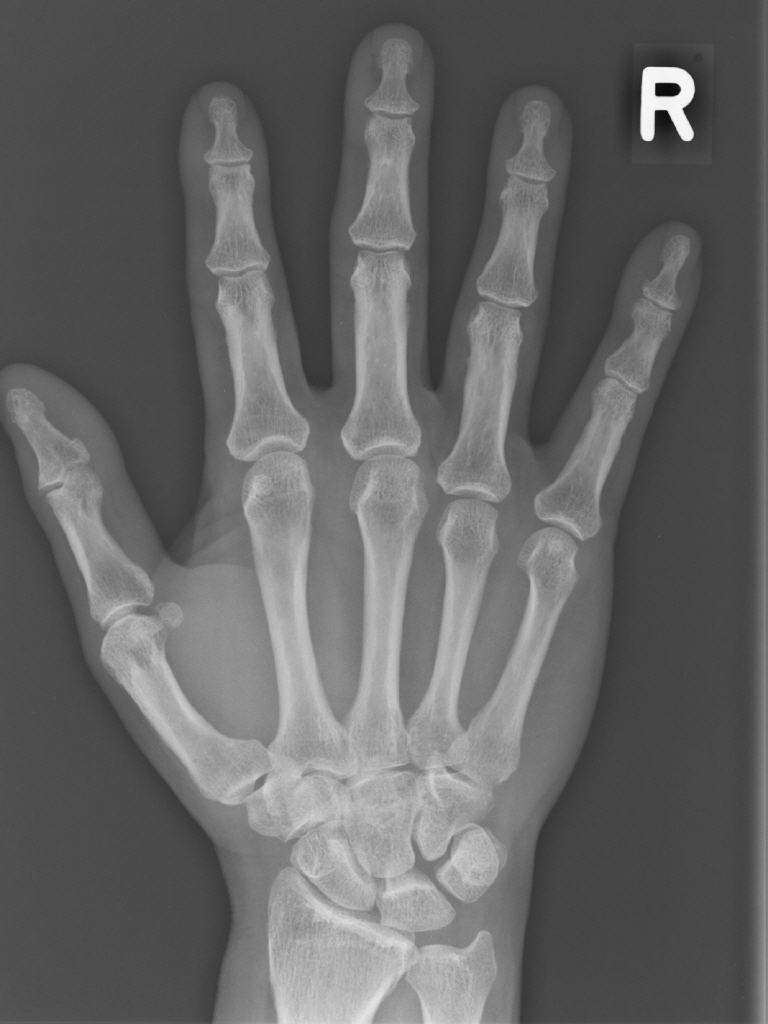

- Aufnahmen der Knochen und Gelenke